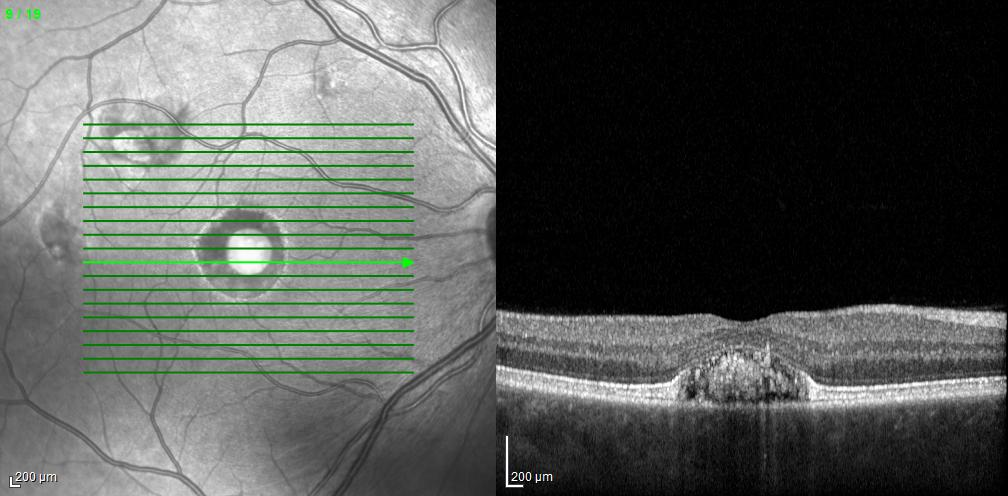

Optical coherence tomography (OCT) through the right fovea reveals a neurosensory detachment with nonreflective material beneath the superior foveal photoreceptors and reflective material centrally. The layered hyperautofluorescence in the right fovea corresponds to this reflective subretinal material. In addition, there is disruption of the retinal pigment epithelium (RPE) and partial loss of the choriocapillaris at the fovea. OCT through the superior macular lesion in the left eye also reveals reflective subretinal material.